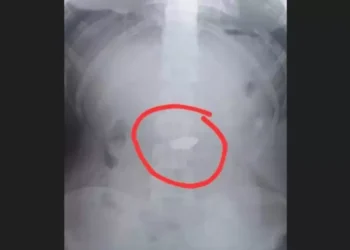

Redação Rios GUARUJÁ (RJ) - Um adolescente de 17 anos foi apreendido sob suspeita de furto e posterior ingestão de ...